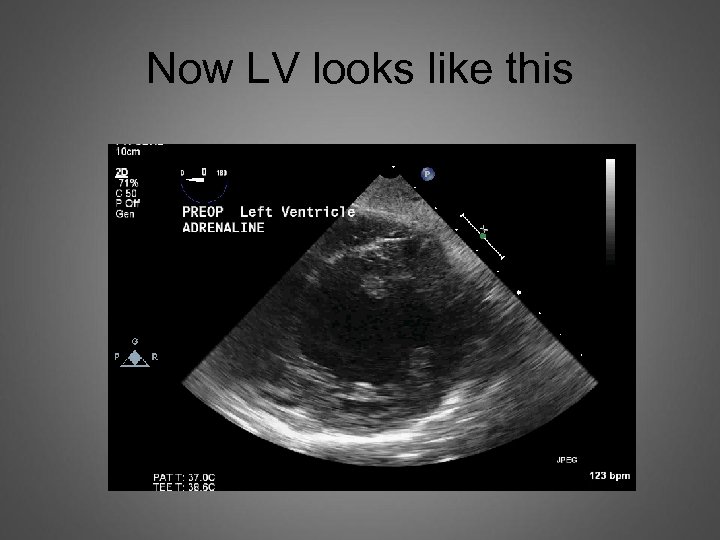

Comment on LV LVESWT =1. 6 cm

Next case LV SAX view

Now LV looks like this